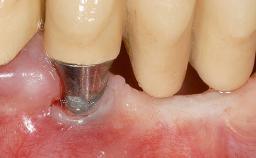

Early Implant Placement, Contour Augmentation, and Autologous Connective-Tissue Graft Using a Tunneling Technique to Replace an Upper Incisor with Generalized Gingival Recession

Variations in soft-tissue volume, evidenced either by an overabundance (Evian and coworkers 1993; Levine and McGuire1997; Dolt and Robbins 1997) or by a deficiency of soft or hard tissue can complicate implant-supported rehabilitations in the esthetic zone (Lorenzana 2008; Lorenzana and coworkers 2009). The present case illustrates the replacement of a failing upper left lateral incisor complicated by generalized severe gingival recession in the esthetic zone.

| Soft Tissue Grafting | Simultaneous |